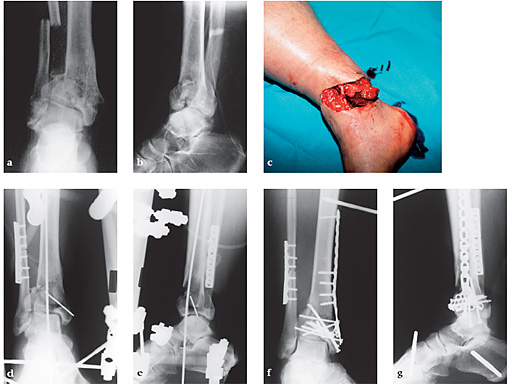

First clinical use of the new pilon plate (2001, Dresden). 39-year-old man fell 3 meters. Open C2.2 fracture treated immediately with debridement, fibula fixation, tibio-tarsal transfixation and vacuseal-dressing. 7 days later secondary A. dorsalis pedis flap after joint reconstruction and pilon plate fixation.

ac Injury x-rays of open injury.

de Primary treatment with external fixator.

fg Postoperative x-rays.